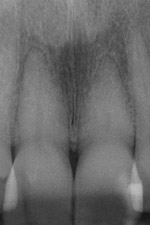

The feature case of this article, highlighted in Figure 13 through Figure 24, demonstrates a comprehensive shift in many aspects of endodontic access. The calcified central incisor (Figure 13) of a 42-year-old woman was treatment planned for elective endodontics to facilitate internal bleaching for esthetic reasons. The preoperative radiograph demonstrated almost complete obliteration of the pulp, except for a small pouch in the center of the root. Referring these challenging cases to a microscopeequipped endodontist should always be considered. However, many well-trained general dentists attempt these difficult cases, and most dentists routinely deal with partially calcified cases. Still, the concepts forwarded in this case can be employed as indicated in every endodontic access treatment.

Fig. 13 Preoperative view of calcified tooth that had been discolored for 25 years.

Figure 13

Fig. 21 Preoperative condition with normal calcification of tooth No. 8 and advanced calcific degeneration of the pulp of tooth No. 9.

Figure 21